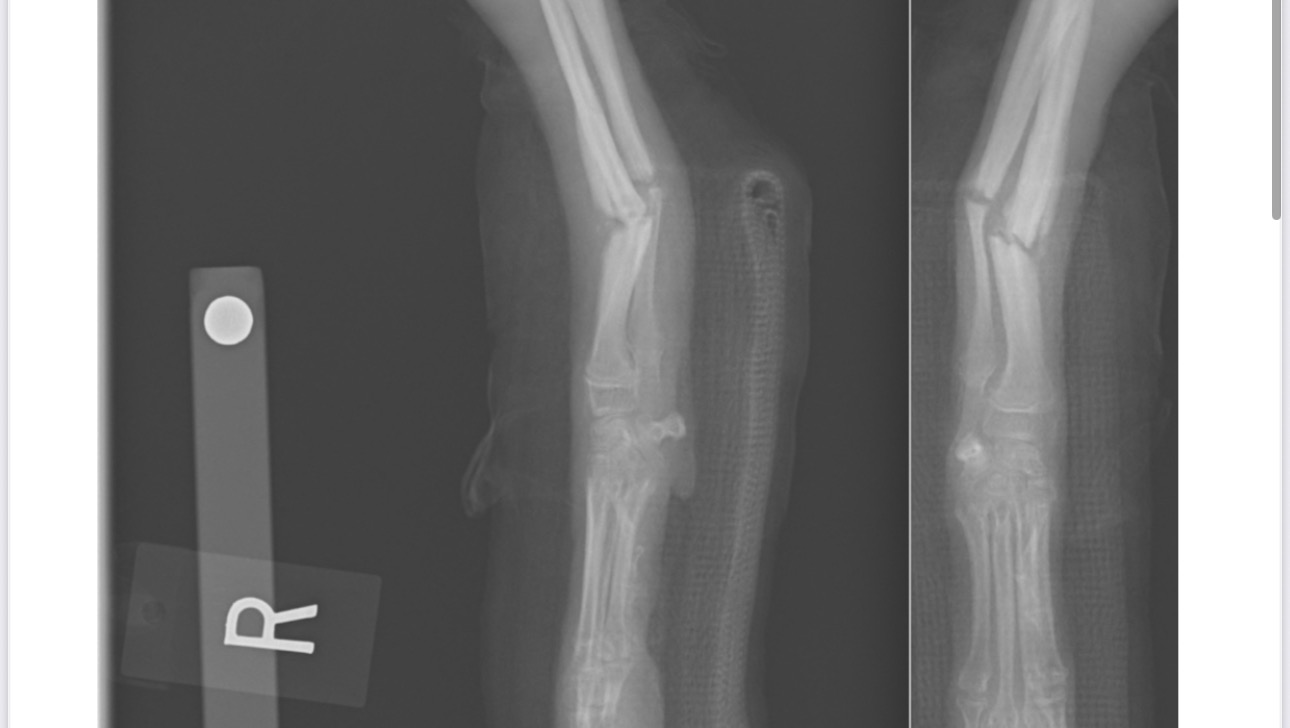

Not long ago, he broke his right leg — we fought hard for his recovery, and only recently had his bandage removed. His leg is still weak and needs careful rehabilitation.

Unfortunately, another tragedy has happened — Bobby has now broken his other leg.

He can barely walk, he is in a lot of pain, and cries and whines almost constantly. Without urgent surgery, he won’t be able to recover.

For now, to stabilize his condition while we wait for surgery, the doctors have placed a temporary bandage on his injured leg. But this is not a permanent solution — he needs surgery as soon as possible to heal properly and avoid further complications.

All medical documents and files are attached below.